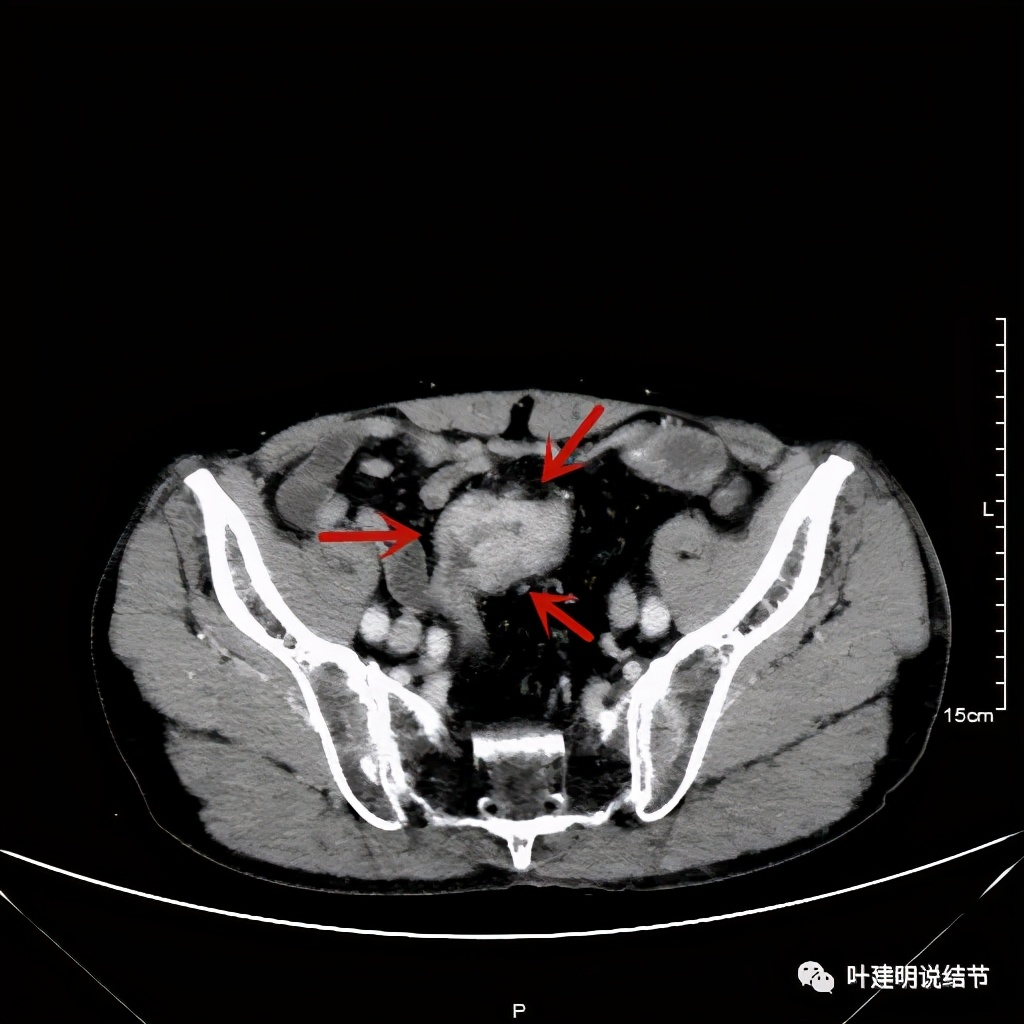

活检后食管是鳞癌,结肠是腺癌。下面是其术前CT的图像:

以上诸图红色示乙状结肠肿瘤,绿色示其下方正常的乙状结肠及直肠